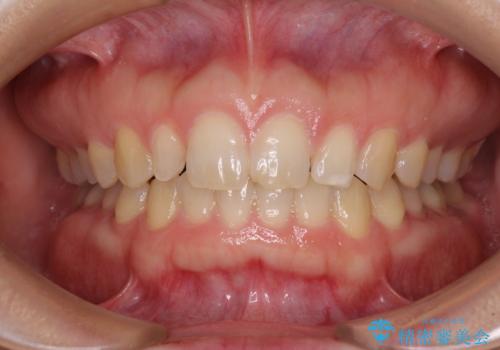

前歯の歯並びと小さい歯を改善 インビザラインとオールセラミッククラウン

- 前歯の空隙と矮小歯を気にして来院された患者様です。

上下の歯列不正はインビザラインにより整えることとしました。

矯正治療の後に、前歯1歯と奥歯をオールセラミックにて治療することとしました。

矯正治療により矮小歯前後にスペースを作りながら歯列を整え、セラミッククラウン装着後に最終的に歯列と咬合を仕上げました。